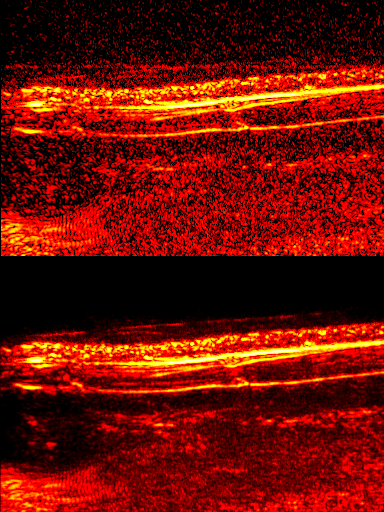

Unsupervised Deep Denoising

One of the main drawbacks of deep learning is the need for lots of high quality training data. A research interest of mine is finding self supervised methods that require no labels and/or can be trained using only the data of interest. Here, a network is trained to predict video frames from previous frames. It is able to learn correlated signals, but has too few parameters to learn high entropy noise - producing a video with reduced noise